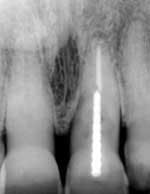

REVIEWING case photos and radiographs …

… communicates how far patients have come with implant TREATMENT.

Radiograph of 71-year-old woman before and after implant restoration

Photos of same woman before treatment

The case above is an excellent example in which someone who experiences continued periodontal breakdown around teeth despite treatment will fare better with implants and resist problems with future decay. Dr. Andrew Alpert of Aventura, Fla., placed the implants.